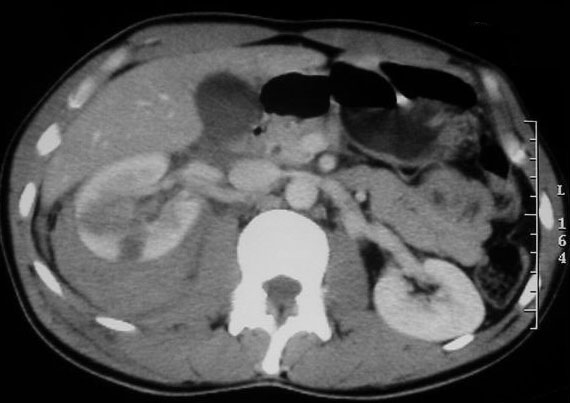

CASO 2: Paciente de 68 años con dolor en flanco izquierdo, fiebre y malestar general. A la exploración existe enrojecimiento de la piel con sensación de masa palpable y puño percusión muy positiva.

El paciente es alégrico al Iodo. Se realiza TC sin contraste para ampliar estudio.

Todos estos hallazgos están en relación con una Pielonefritis Xantunogranulomatosa que afecta al riñón derecho junto con una colección que ha fistulizado a región lumbar.